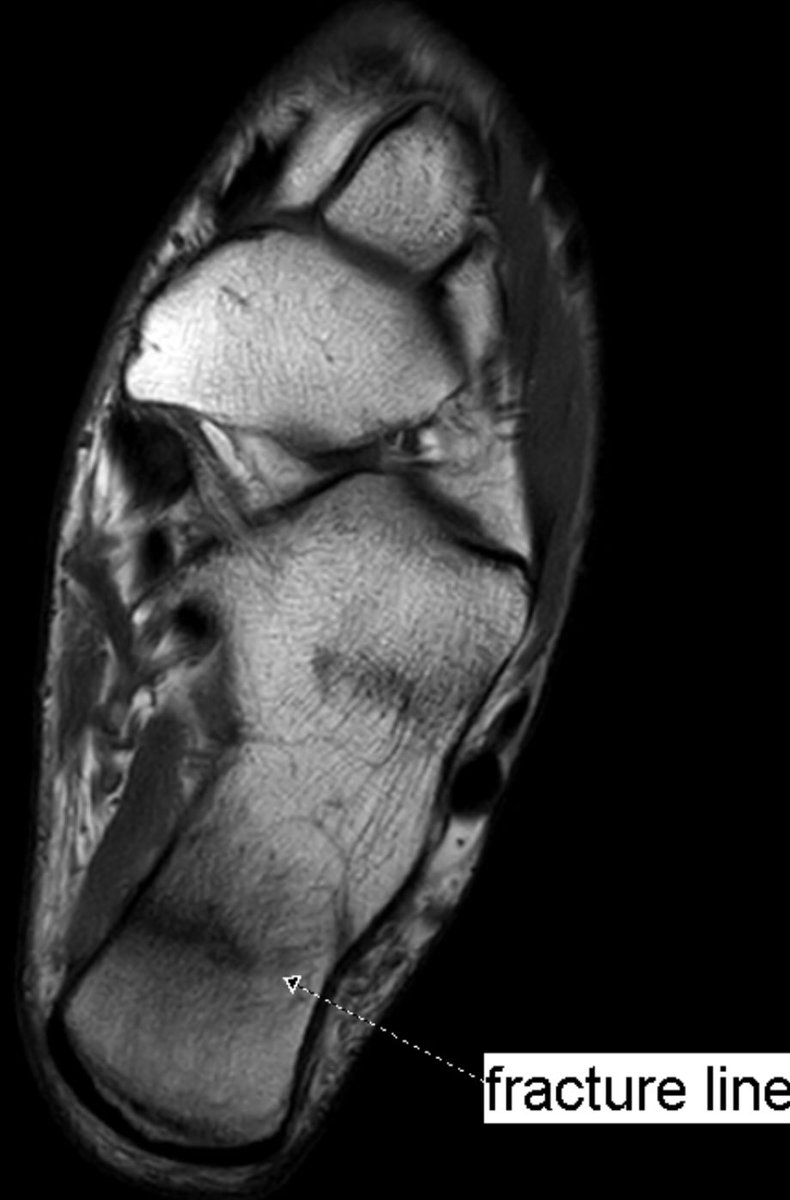

Pain worsening after rest. New MRI 18 days after to rule out again stress fracture, now clearly seen. Back to baseline examination, the oblique fracture plane was better seen as a subtle line in sagittal images.

#peerlearning#MSKrad#foot#orthopaedicspic.twitter.com/HtDYoFvH8V